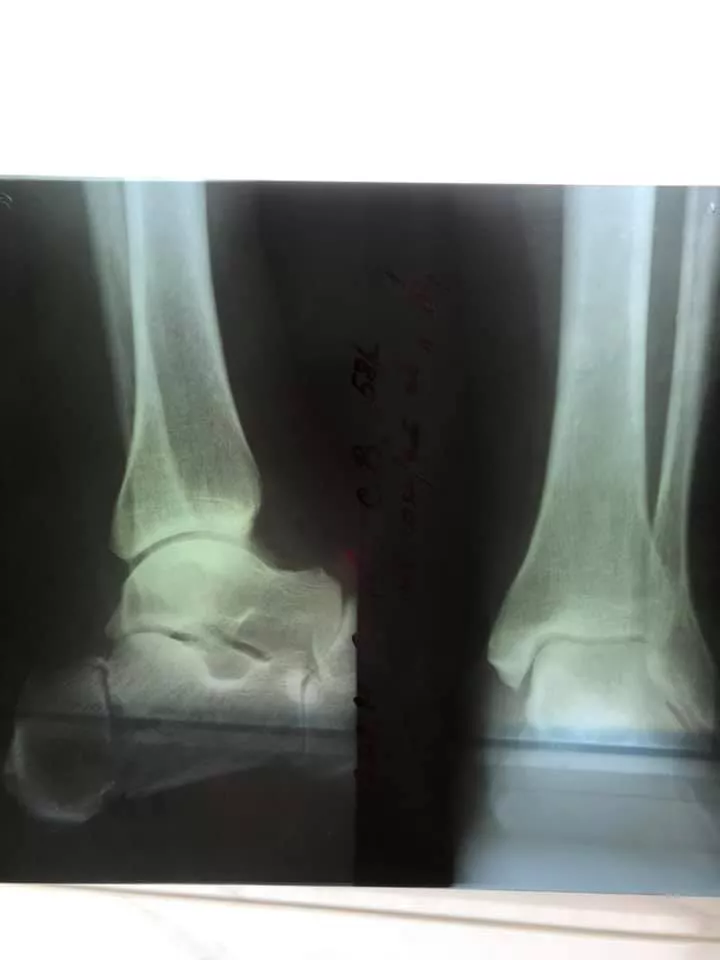

Після проведеного обстеження пацієнтки встановили діагноз: відламковий перелом п‘яткової кістки зі зміщенням.

Під СМА (спинно-мозкова анестезія) провели остеосинтез п‘яткової кістки. Операція пройшла успішно. У пацієнтки були відновлені активні рухи в суглобах стопи.